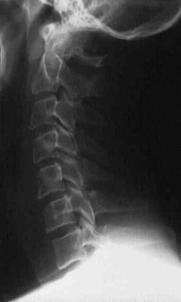

Fracturi simple: SPIRALA OBLICA TRANSVERSALA

Fractura spirala de Fractura transversa de diafiza femurala Fractura spirala de diafiza tibiala

diafiza humerala

Fractura spirala de diafiza tibiala Fractura oblica de diafiza tibiala Fractura transversala de diafiza tibiala

Fracturi cominutive

Fracturi spirala cominutive de Fractura complexa de diafiza radiala diafiza humerala